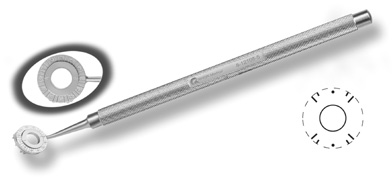

The extent of arc to be incised may be demarcated in several different ways. Our preferred method makes use of a modified Fine-Thornton fixation ring (Nichamin Fixation Ring and Gauge; Mastel Precision, Storz, Rhein Medical). This instrument serves to fixate and position the globe in order to optimize incision placement, as well as to delineate the extent of arc to be incised. One visually extrapolates from the limbus to marks on the surface of the ring. Each incremental mark is 10 degrees apart, and bold hash marks (180 degrees) opposite to each other serve to align and center the incision over the steep meridian. This approach obviates the need to ink and physically mark the cornea. If one desires, particularly when first gaining experience with LRIs, a two-cut RK marker may be used to place ink marks upon the cornea to show the exact extent of arc that is to be incised, in conjunction with the fixation ring/gauge (Fig. 4). Alternatively, various press-on markers are available, such as those made by Rhein Medical (Dell-Nichamin Marker, Nichamin-Kershner Marker, or the Ruminson Marker) (Fig. 5). ASICO and other instrument companies offer a full line of dedicated markers, rings, and blades for performing LRIs.

Fig. 4. The Nichamin Fixation Ring and Gauge serves to both fixate the globe and delineate the extent of arc to be incised; a two-cut radial marker may be used to mark the extent of arc to be incised, and the Mastel Nichamin Force AK Diamond Blade with preset depth of 600 microns.

Another less common method of creating peripheral relaxing incisions is to use a device such as the Terry/Schanzlin Astigmatome (Oasis Medical), which circumvents the need to make a “free-hand” incision. This trephine-like device has been designed to create consistent and symmetric peripheral arcuate corneal relaxing incisions. It uses a vacuum speculum that mates with various reusable templates that are selected based upon the amount of astigmatic correction that is desired. The incision is created by simply rotating a disposable steel blade unit that fits inside of the template (Fig. 7).

Fig. 7. The Terry/Schanzlin Astigmatome.